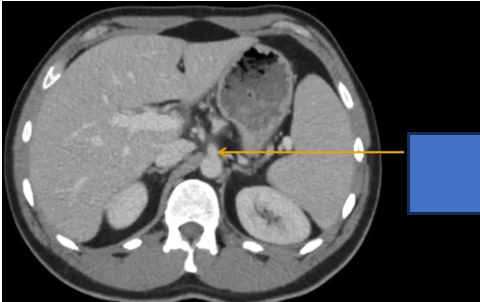

đm thận T?